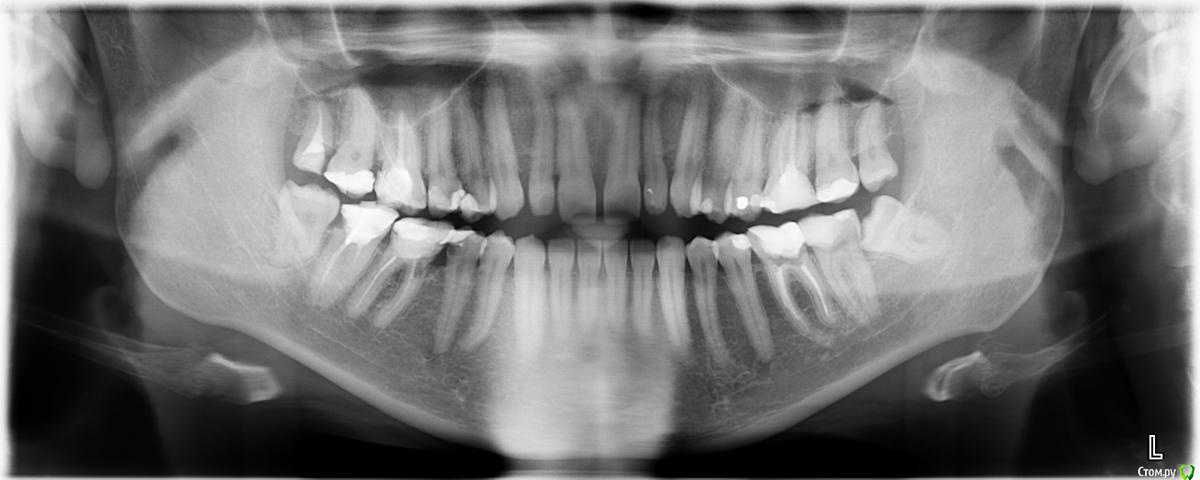

alex0814 Опубликовано 19 июня, 2015 Поделиться Опубликовано 19 июня, 2015 Здравствуйте! Собрался протезировать сильно разрушенные жевательные зубы. Прошу консультации: какие зубы, по вашему мнению, уже не вылечить, а только удалять и имплантировать? И имеет ли смысл оставлять какие-нибудь из восьмерок? P.S. Очно консультировался в одной клинике, там предлагают удалять и потом имплантировать 26, 45, 46, 47. Ну и все восьмерки долой. Ссылка на комментарий

Bier Опубликовано 19 июня, 2015 Поделиться Опубликовано 19 июня, 2015 Судя по снимку удалять все восьмерки и 46з. Остальное по снимку вроде как можно сохранить, возможно чего то на снимке не видно. 3 Ссылка на комментарий

Гарриевич Опубликовано 21 июня, 2015 Поделиться Опубликовано 21 июня, 2015 46 и 47 и 26 по снимку действительно плохи, но надо еще прицельные снимки посмотреть45 нормально, тем более что 46 на удалениевосьмерки на удаление Ссылка на комментарий